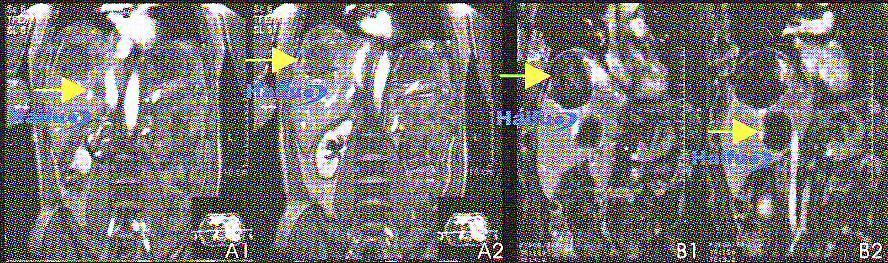

4. МРТ-сканы с контрастным усилением гандолинием пациента с двумя узлами гепатокарциномы, которому проводилось однократное лечение

HIFU. Одна опухоль располагалась под диафрагмой, другая рядом с нижней полой веной.

А1, А2) До HIFU. В правой доле печени визуализируется два образования (стрелки).

В1, В2) Через 2 недели после процедуры HIFU. Отсутствие накопления контраста подтверждает наличие коагуляционного некроза в обеих узлах опухоли (стрелки).

5. МРТ-сканы с контрастированием гандолинием (Т1-ви) 36-летней пациентки с раком молочной железы:

Аксиальные (А1) и сагиттальные (В1) срезы пораженной железы до HIFU.

Соответствующие срезы (А2 и В2), через неделю после сеанса HIFU. После лечения накопление контрастного вещества в опухоли не происходит (стрелка).